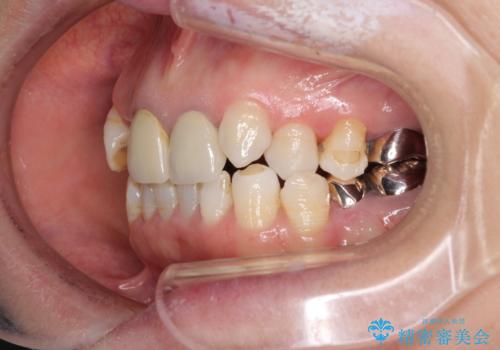

- 全顎的な歯列不正と、銀歯だらけの奥歯を気にして来院された患者様です。

奥歯の銀歯は、セラミッククラウンを装着するには歯の高さが不十分であり、そのままでは矯正治療を行うことが困難であるため、歯冠長延長術を行うこととしました。

また、根管治療の必要な歯がいくつかあるため、歯周外科治療の治癒期間を利用して根管治療を行い、その後インビザラインにて矯正治療を行うこととしました。